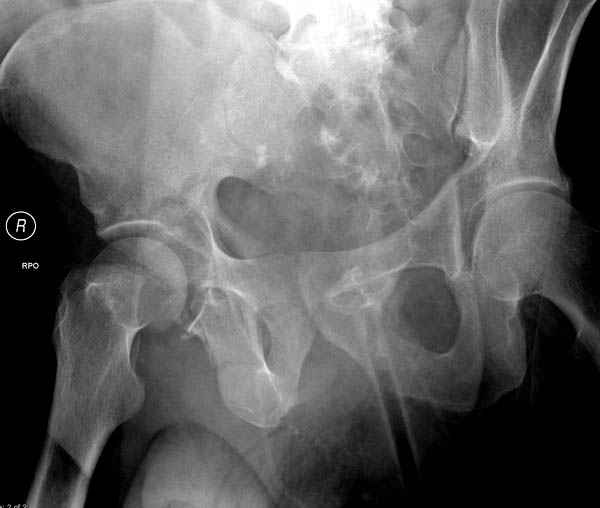

колонна с полупоперечным переломом, и переломы костей лица.

На седьмой день зафиксирован перелом ацетабулума через задний доступ. Перед операцией для профилактики DVT, IVC фильтер, также получает Lovenox.

Очень хорошаая работа, поздравляю! Хотелось бы увидеть снимок таза до операции. Каким образом и как долго предполагаете разгружать тазобедреннй сустав в дальнейшшем?

Отправитель: Evgueny Tchekashkine 30 Ноябрь 2007, 16:57

По возможности вышлите снимки, сканы таза до реконструкции, интраоперационные.

По снимку создается впечатление о высоком поперечном переломе, задней колонны, стенки; почему не пользовались *magic screw*?

Положение больного на животе или на боку?

Кава фильтр при переломах таза - это протокол или только для пациентов с политравмой?

Фиксация таза до реконтструкции с момента поступления? Когда начали DVT профилактику: сразу при поступлении или накануне реконструкции?

По возможности вышлите снимки, сканы таза до

реконструкции, интраоперационные.

Не хотелось отклонятся от основной темы, поэтому здесь краткие ответы..

Латеральное положение облегчает проведение тракции через вертел, за 5 мм стержень за вертел (грузом через тракционное приспособление), на обычном рентгенопрозрачном операционном столе, а для положения на животе, наверное, Judet Table более приемлем, потому что там имеется латеральное тракционное устроиство.

Там множество обычных 2.7 мм шурупов, потом идет фиксация основными пластинами.

Профилактику DVT и установку кава фильтер применям

почти у всех со множественными травмами, особенно тем, кто потенциально должны находится длительно без активного движения, тем более тем, кто страдает избытком веса.

В нашем протоколе в день операции делаем допплеровскую проверку сосудов, и в координации с сосудистыми хирургами установку фильтра до начала нашей операции, современные фильтры временные, можно удалить через несколько месяцев.

Полную нагрузку разрешаем в 12 недели, хотя движения в суставе с первых дней.

Снимки здесь....